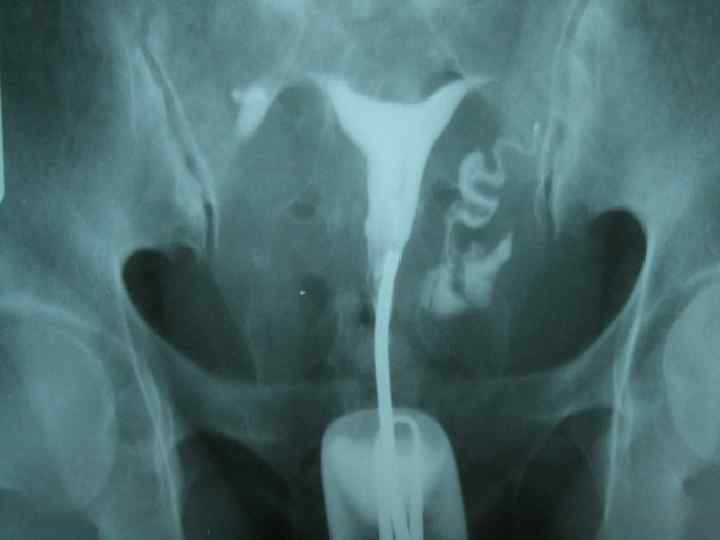

• Гистеросальпингографией (ГСГ) называют метод рентгенодиагностики состояния фаллопиевых труб и внутренней полости матки, их проходимости и строения при помощи введения контрастного вещества в полость матки и труб. Основные показания • • бесплодие, не связанное с нарушением обмена гормонов, трубное бесплодие или подозрение на него, патологии внутри матки – полипы, миомы, эндометриоз, гиперплазия эндометрия, подозрение на туберкулез половых органов, аномалии развития матки и маточных труб, инфантилизм матки, подозрения на внутриматочные и трубные спайки, подозрение на истмико-цервикальную недостаточность.

Методика проведения • Время проведения процедуры зависит от целей исследования и предполагаемого диагноза, который необходимо подтвердить или опровергнуть при исследовании. • Для изучения проходимости труб или состояния шейки матки гистеросальпингография назначается во вторую фазу цикла • Если есть подозрения на эндометриоз матки – на 7 -8 день цикла • При подозрении на миомы матки срок значения не имеет, главное, чтобы не было менструации.

Проведение • Для проведения гистеросальпингографии применяют водные растворы контраста - верографин, уротраст, кардиотраст. Процедура проводится на особом гинекологическом кресле, не дающем помех на рентгене. • Перед началом процедуры врач проводит общий гинекологический осмотр женщины – двуручный, а затем применяются зеркала. В область шейки матки вводится небольшая канюля-трубочка, присоединенная к шприцу с контрастным веществом. Через нее вводится контраст в полость матки, заполняет ее и переходит в область маточных труб. • По мере заполнения веществом полости матки и труб делается серия рентгеновских снимков, вещество отражает рентгеновские лучи и показывает внутренние контуры матки и труб. После выполнения снимков врач извлекает канюлю, остатки вещества выделяются из матки или всасываются в кровь и выводятся из тела. • Обычно процедура проводится без наркоза, либо под местной анестезией. При проведении процедуры возникают небольшие проявления болезненности внизу живота, особенно при заполнении полости матки и труб, проходящие в течение получаса после процедуры.